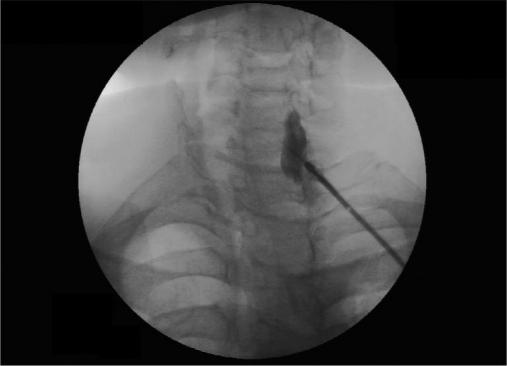

Stellate ganglion block (SGB) is very effective in management of chronic regional pain syndrome (CRPS-1). However, serious complication may occur due to accidental intravascular (intra-arterial) injection of local anaesthetic agents. Abdi and others, has suggested a modified technique in which fluoroscopy-guided block is given at the junction of uncinate process and body of vertebra at C7 level. In this approach vascular structures remain away from the trajectory of needle and thus avoid accidental vascular injection. We have used this technique of SGB in nine patients who were treated for CRPS-I. The blocks were effective in all the patients all the time without any vascular or other serious complication.

星状神经节阻滞(SGB)在慢性区域疼痛综合征(CRPS-1)的治疗中非常有效。然而,由于局部麻醉剂意外血管内(动脉内)注射,可能会发生严重并发症。阿卜迪等人提出了一种改良技术,即在C7水平的钩突与椎体交界处进行荧光透视引导下的阻滞。在这种方法中,血管结构远离针的轨迹,从而避免意外血管内注射。我们对9例接受CRPS-I治疗的患者使用了这种SGB技术。所有患者的阻滞始终有效,未出现任何血管或其他严重并发症。